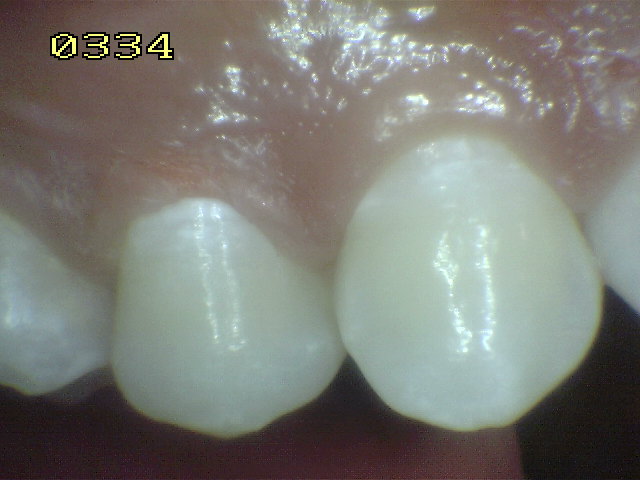

Esmalte liso, traslúcido y

cristalino acompañado con gruesas líneas

horizontales blanquecinas. |

Las manchas opacas por fluorosis leve deben

diferenciarse con los códigos1 y 2 de ICDAS. En las

fluorosis el esmalte aparece brillante; mientras que

en el proceso de caries se observa un blanco aspecto

de tiza. (sin brillo) |